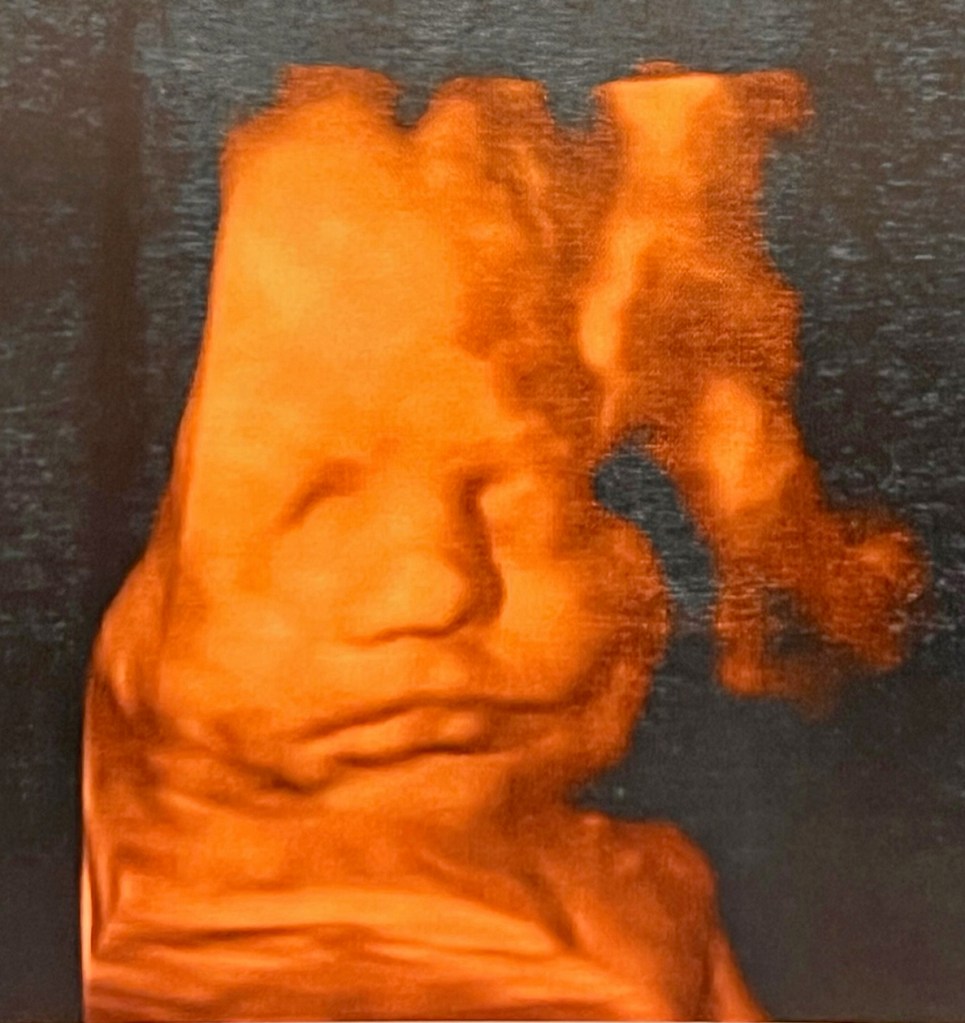

though we had seen you only in

fuzzy black and white scans, your

little face mooshed up inside your

mama, whose voice you already knew,

Henry in utero at 30 weeks,

son of Lauren Just Giel and Gerald Giel